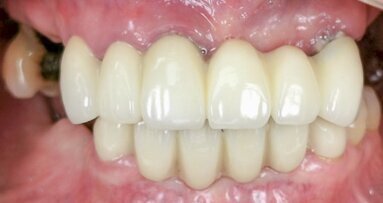

The following clinical case report presents the successful treatment of bilateral sites using both immediate and conventional implant placement with the ...